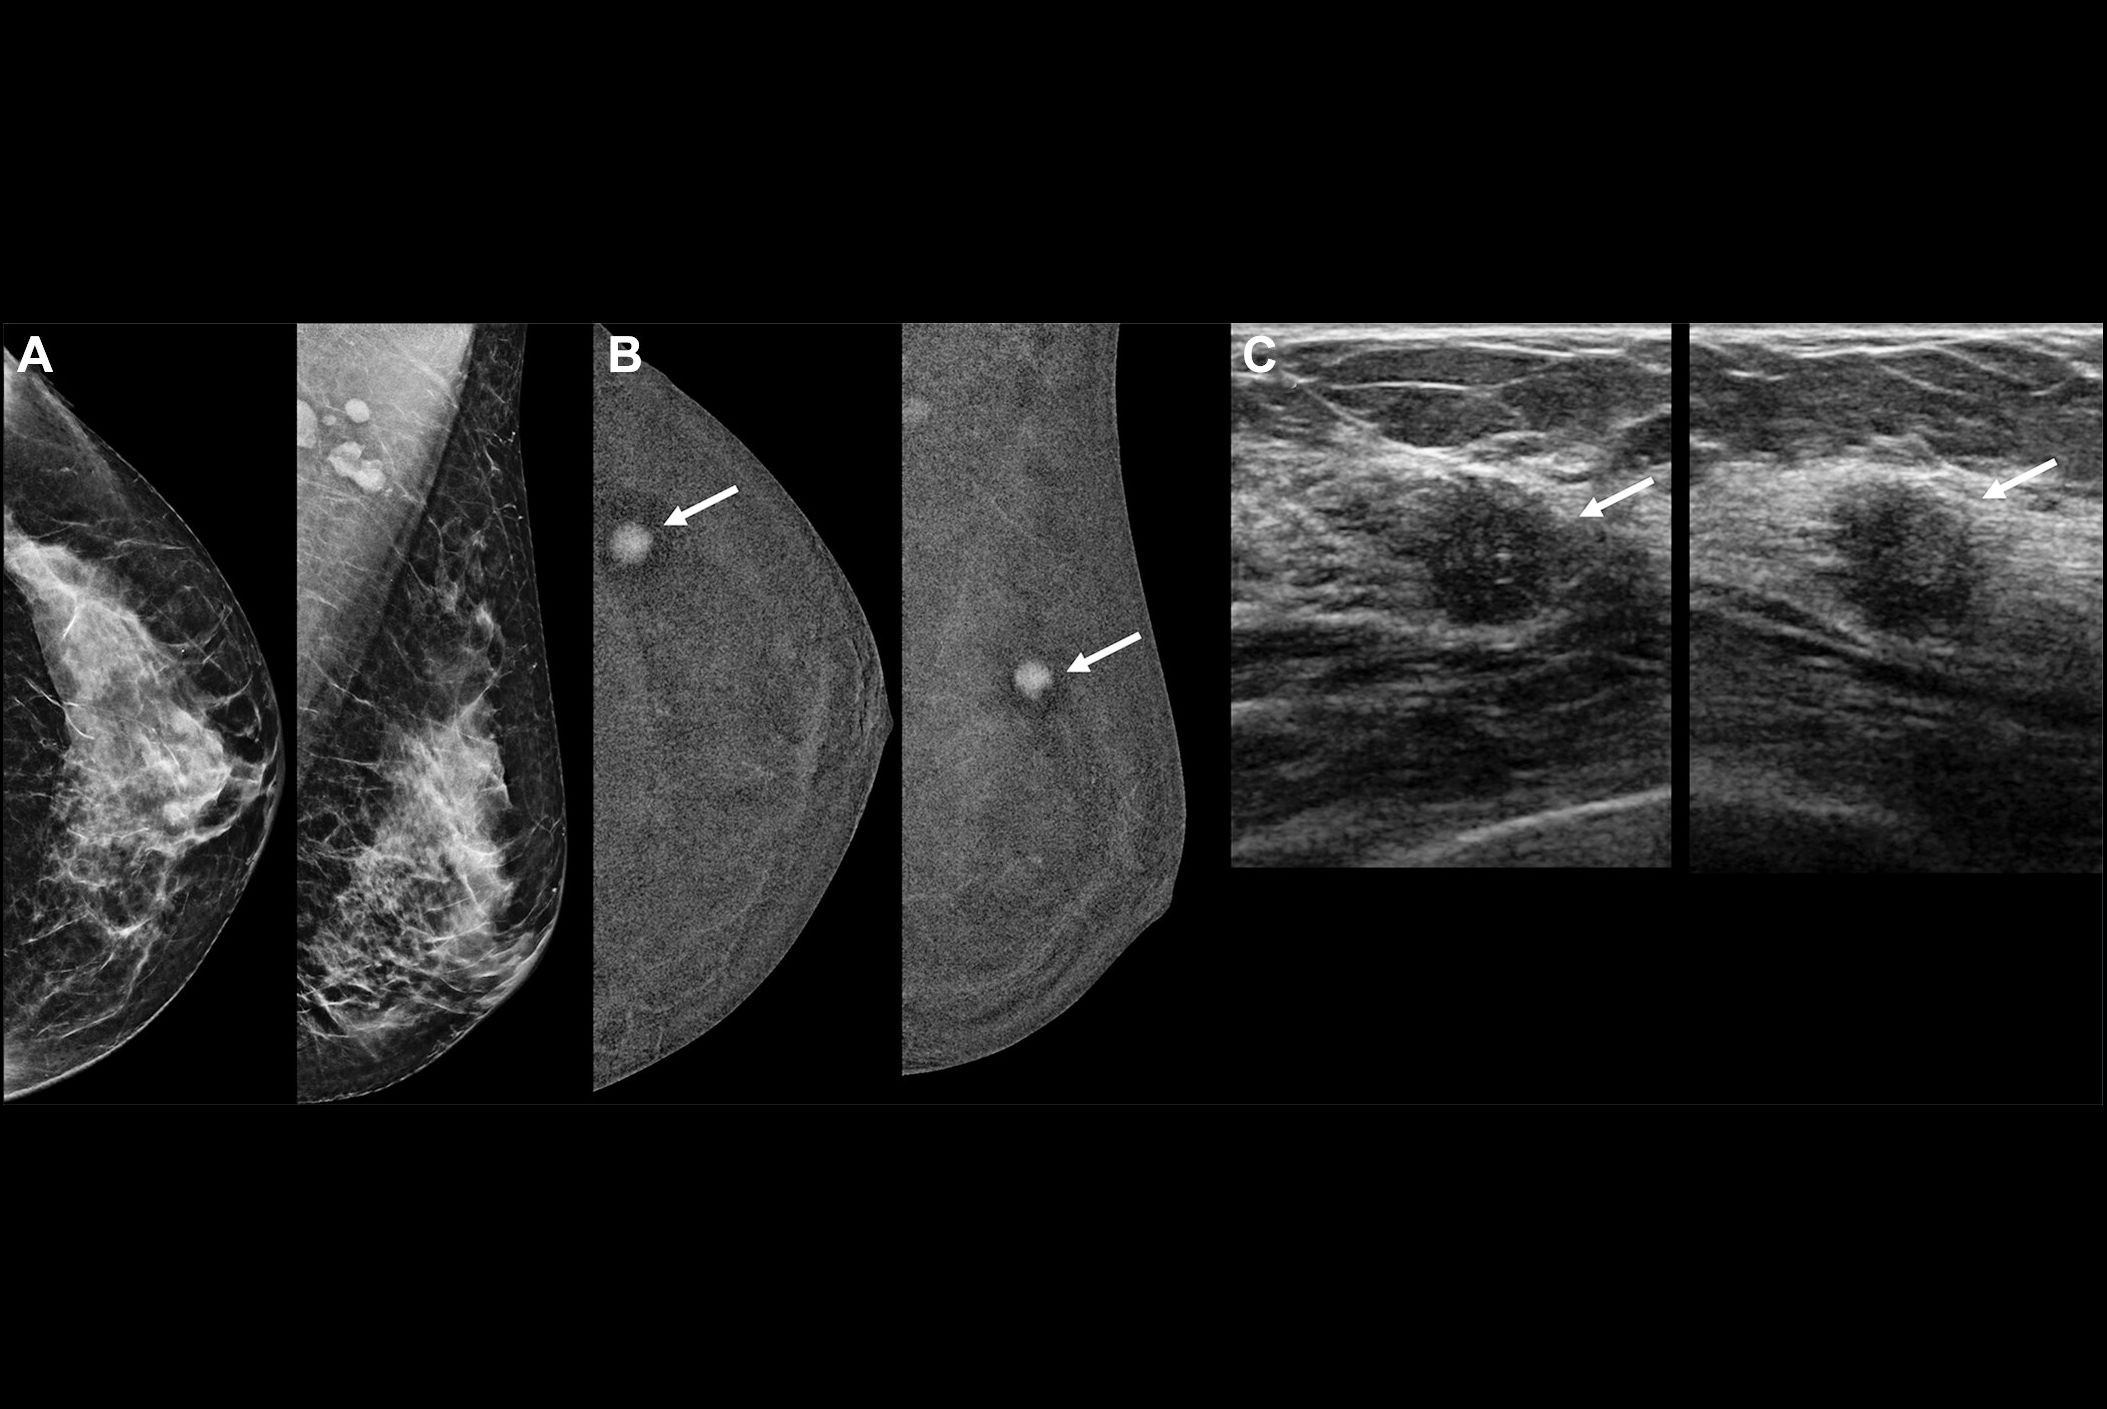

Mammography is the traditional modality for both screening for breast cancer and follow-up of suspicious results, but it has its limits, notably less ability to identify cancer in dense breast tissue. Ultrasound offers another screening tool and can overcome some of mammography's limitations. But contrast-enhanced imaging shows promise for breast cancer diagnosis in that it provides functional information regarding tumor vascularity that "strongly boosts the cancer detection rate in screening and also improve staging," the team explained.

- When compared with standard mammography for diagnosing breast cancer, CEM has shown improved sensitivity (90.5% vs. 52.4%) but also reduced specificity (76.1% vs. 90.5%). Previous research has estimated breast MRI's sensitivity to be up to 100% and its specificity up to 98%.

- One of CEM's main limitations compared to breast MRI is its lower ability to visualize the axillary regions of the breast.